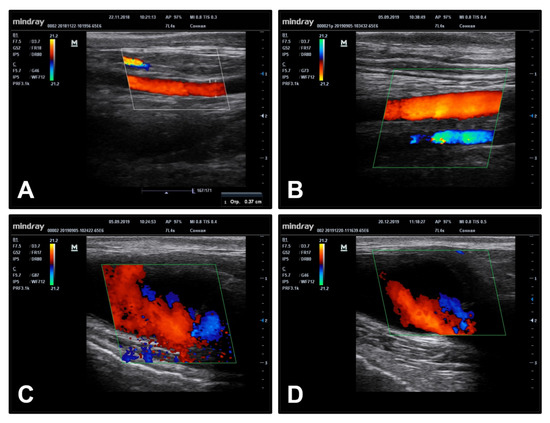

3.4. Hep/Ilo Coating Endows TEVGs with a Considerable Long-Term Primary Patency